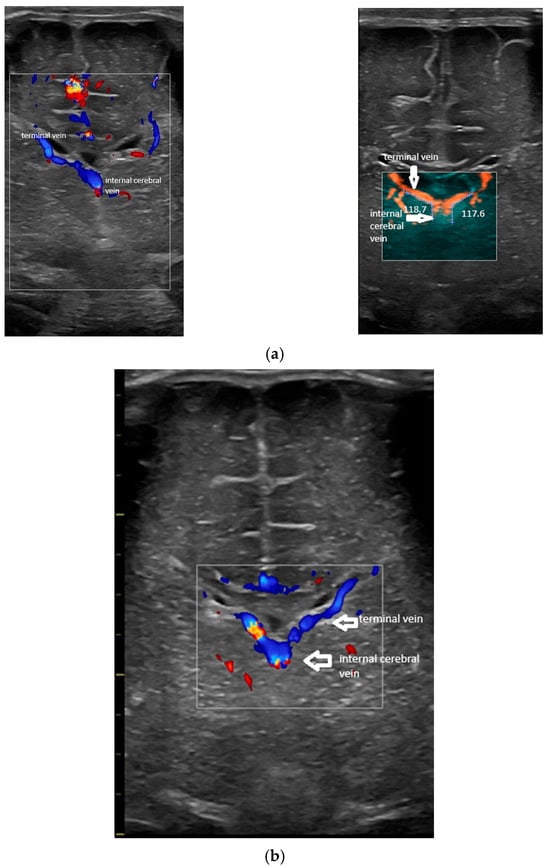

- Confluence at the level of the foramen of Monro (Figure 2).